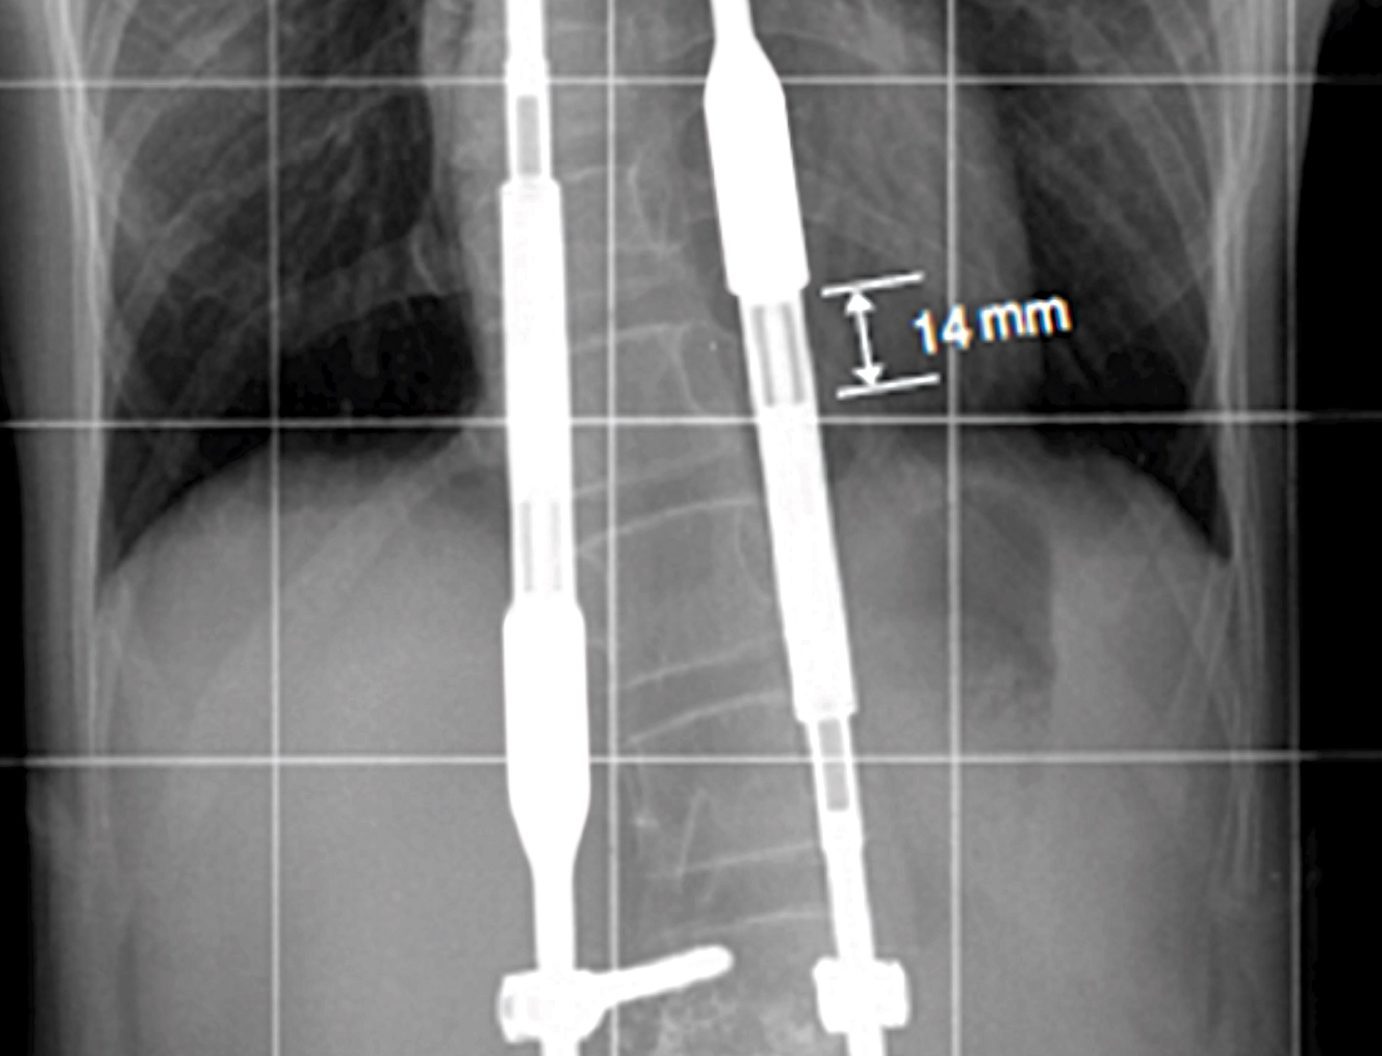

Sin embargo, la Clínica Mayo asegura que, en algunos casos, se indica el uso de un corsé ortopédico para frenar la progresión de la curvatura, o se recurre a cirugía correctiva cuando la desviación es severa.